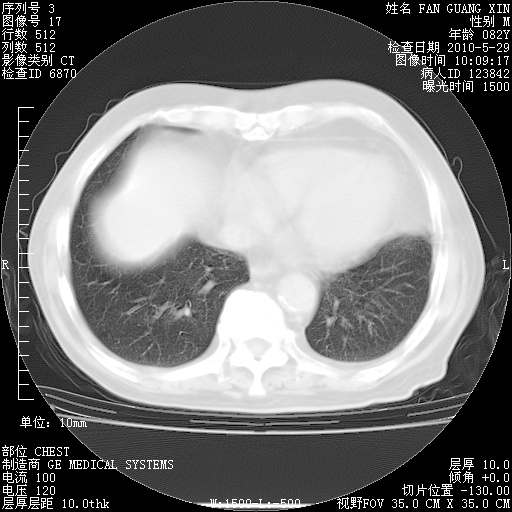

再治疗10天后的肺部CT

再治疗10天后的肺部CT 纵膈窗

从白细胞总数和中性比例看好像合并感染。肺部纹理好像比上次多,支气管炎?其他感染?

阅读此次胸部CT,肺间质渗出性改变较入院时有吸收。目前从体温、白细胞、中性分叶明显增高,肯定存在细菌感染(发生医院感染哦,若无消化道及泌尿系统等感染的依据,肺部感染可能大)。若你院头孢哌酮舒巴坦钠耐药率较高,同意你的方案,若48小时体温仍高,可考虑使用碳青霉稀类抗菌药物,同时可予超声雾化、注意滴数时加大液体量。白蛋白33.30g/L较低哦,需加强营养等支持治疗。